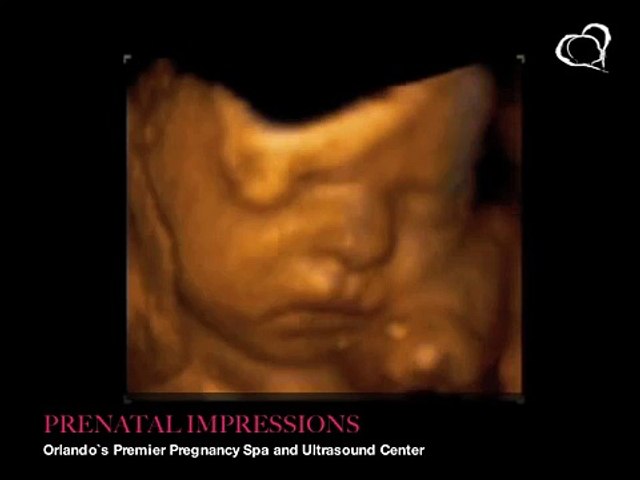

26 Weeks Pregnant 3d Ultrasound

4d ultrasound 26 weeks pregnant face 4d rafael ortega munoz md ciudad real duration. Ecografia 4d 3d dr. My favorite was the 25 week ultrasound. Rafael ortega munoz ginecologo especialista en ecografias 4d.